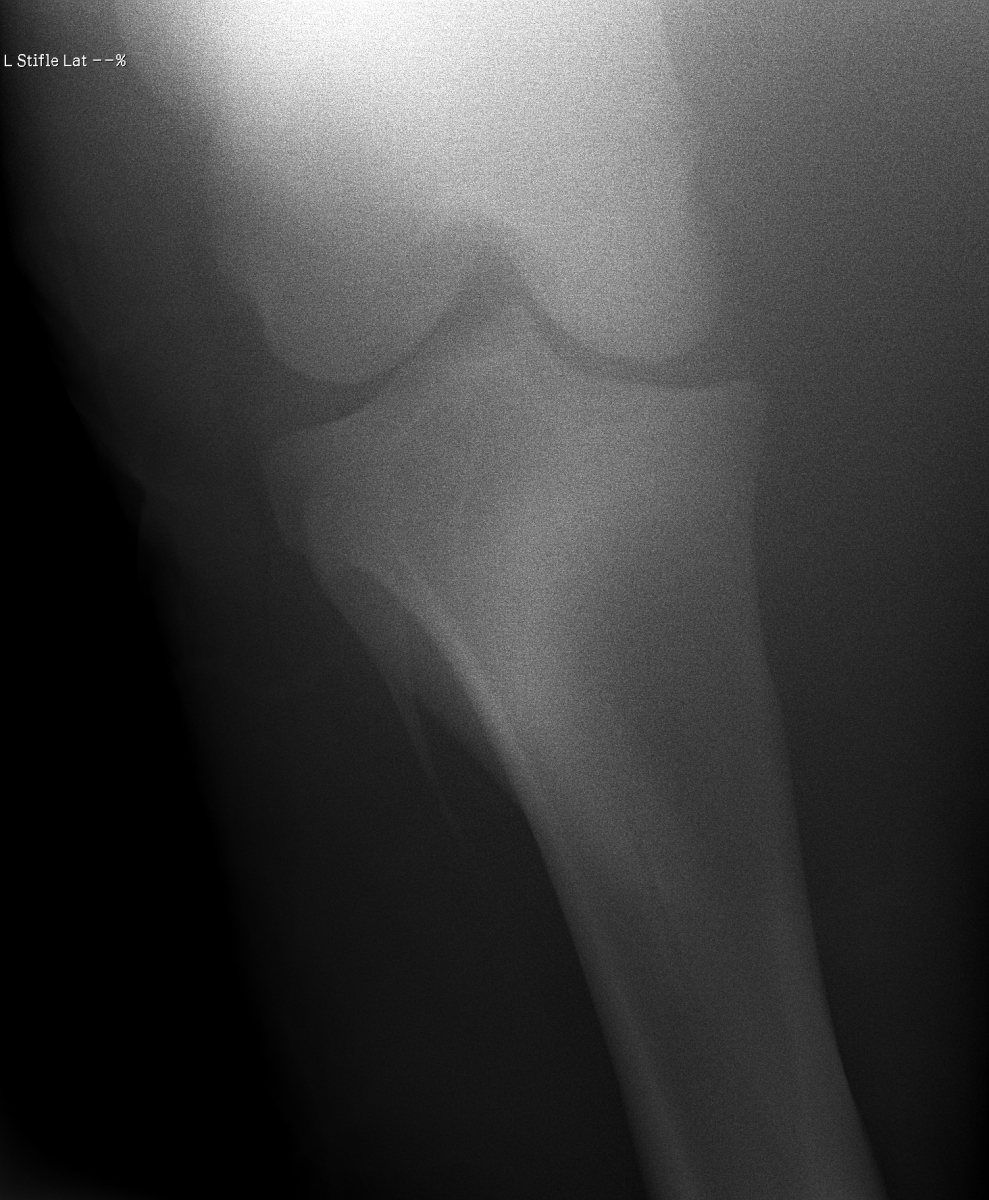

添付のレントゲン画像をご確認ください。現状渡しのノークレームノーリターンでお願いいたします。記載事項に関するキャンセルには応じられません。

前走で暴れた際にひねって、ヒビが入ってしまったのではないかと思われます。舎飼にて安静を保ち、時間を掛けて自然治癒を待つ他なく、早くても実戦復帰まで半年は要すでしょう。テンションのコントロール、ゲート枠内での駐立不良をなんとかしようと試行錯誤してアプローチしてみましたが、結果を出すことができませんでした。なお、興奮時にDDSP(軟口蓋背方変位)のような症状をみせることがあります。(船橋競馬・佐藤裕太調教師)

※2022年12月17日の競走にて左後脛骨不全骨折を発症しています(全治6~9ヵ月)。